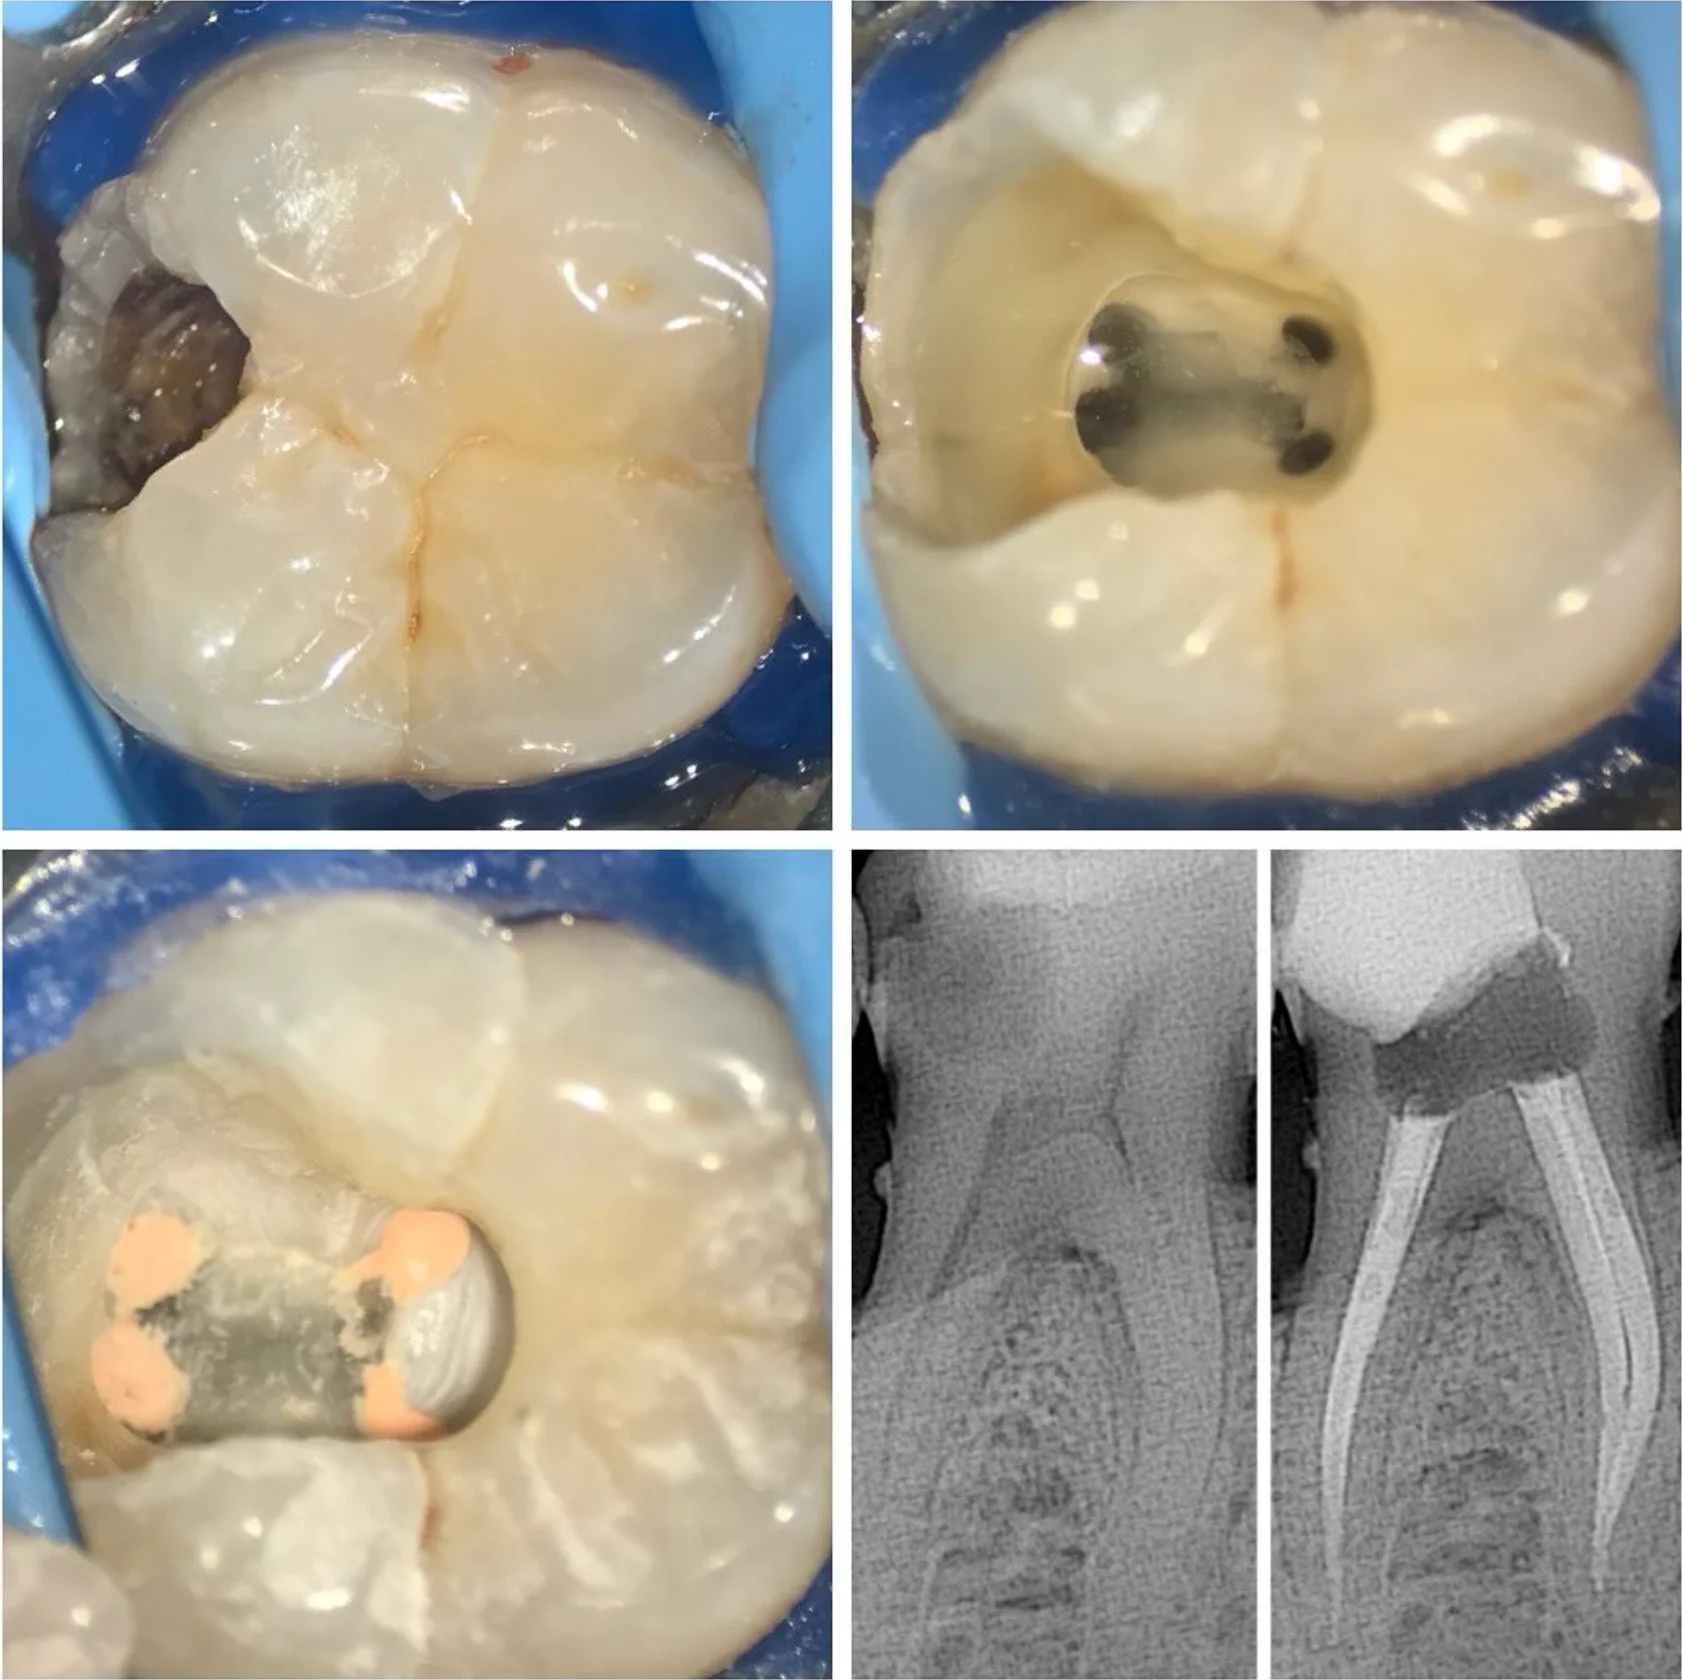

Tedavi Örnekleri

Kliniğimizde gerçekleştirilen kanal tedavisi vakalarından örnekler. Röntgen görüntüleri tedavi öncesi ve sonrası sonuçları göstermektedir.

Daha fazla tedavi örneği için ana sayfamızı ziyaret edin →